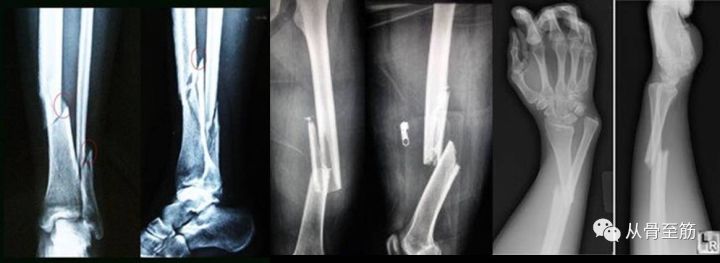

? ? 众所周知:单纯的软组织扭伤有时也会肿得很明显。骨折比软组织扭伤所受到的暴力要大得多,所以局部肿胀会更加明显,软组织损伤也会更重。骨折后短时间内局部即可出现肿胀,严重者几分钟就会明显肿胀。一般会在48-72小时达到高峰,一周左右才能基本消退。如果在此期间手术,骨折与手术创伤叠加在一起,相当于“雪上加霜”,会加重局部软组织肿胀,不利于软组织生长修复,甚至可能造成伤口不能缝合,或虽勉强缝合,但术后出现皮肤坏死、感染、骨外露或钢板外露,严重者可能会出现骨髓炎,那时候麻烦可就大了。软组织损伤、肿胀时局部抵抗力下降,容易成为细菌繁殖的温床。如果此时切开手术,造成细菌植入,极易感染。如果受伤当时,伤情较重,手术还会增加全身各脏器负担,手术风险明显加大。

? ??当然,也不是所有骨折都要等一段时间再手术。受伤6小时以内无明显肿胀的闭合性骨折,如果条件允许可以安排急诊手术。对于开放性骨折在6-8小时以内者,或肿胀严重可能影响患肢血运时一般会安排急诊手术。当然最终还要根据病情、医院的手术室占用情况、医生忙闲、固定器械准备情况综合确定。

? ??对于闭合性骨折,到达医院时已经出现了肿胀,最好是等消肿后再手术治疗。如果没有水泡,待局部皮肤出现皱褶即可;如果出现水泡,应待水泡消退后再手术。